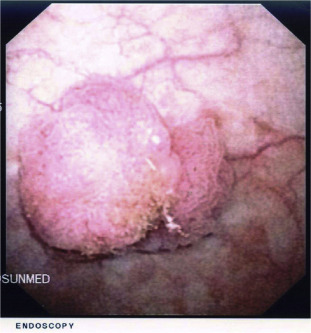

Abdominal computed tomography scan confirmed the bladder lesion with no extra vesical extension. A subsequent flexible cystoscopy showed a solid papillary lesion at the dome of the bladder (Fig. 1) and two smaller lesions in a background of inflamed urothelium (Fig. 2). The patient underwent transurethral resection of the bladder tumor with cystodiathermy, followed by postoperative installation of a single dose of mitomycin C in the recovery suite. The histopathological report confirmed high-grade 3 TCC of the bladder with no carcinoma in situ and no evidence of muscularis propria invasion. He made an uneventful recovery and 2 weeks later an intravesical course of BCG was initiated to reduce the risk of recurrence and progression of the bladder tumor. He received weekly intravesical installation of BCG (81 mg/week) and received 4 weeks of installation uneventfully. However, 2 days before the fifth instillation, the patient reported milky urethral discharge, bilateral red sore eyes, and low backache associated with asymmetrical arthralgias of the hands and feet. There were no preceding flu-like symptoms, lethargy, fever, or any gastrointestinal or urinary tract infections and he had no previous rheumatologic disorders. On examination, bilateral conjunctivitis was identified ( Fig. 3) and the patient had limited back movement due to pain. There were no stigmata of genital cutaneous lesions. Blood test results were largely unremarkable, urine culture did not reveal any bacterial growth, and urethral smear was negative. Routine tests for STD were negative. We suspected Reiters syndrome and BCG treatment was deferred. The patient was then referred to a rheumatologist and an ophthalmologist for their opinions, who confirmed the diagnosis as Reiters syndrome. The patient was treated symptomatically with nonsteroidal antiinflammatory drugs (NSAIDs) for the back pain and with chloramphenicol eye ointment for conjunctivitis. He was then closely monitored in order to initiate treatment with steroids and isoniazid if there was no spontaneous improvement. Fortunately, the conjunctivitis subsided after 8 days of treatment and his backache resolved after 3 weeks. We decided to stop further BCG treatment, and a subsequent cystoscopy check revealed only generalized inflammation with no signs of recurrence. The subsequent follow-up cystoscopies to detect recurrences were essentially normal. Once these aforementioned symptoms resolved, no recurrences of conjunctivitis, arthralgias, or any further urethral discharge was noted.

Cystoscopic view of bladder lesion.